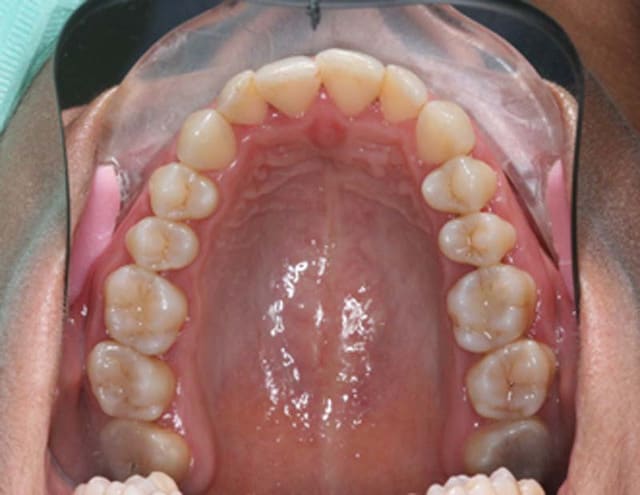

Modèles de départ

traité il y a 3 ans, avec extraction

les photos de samedi suivent

et les photos d'arcades

la patiente est inquiète car malgré la contention Inf.

"ça revient comme avant"